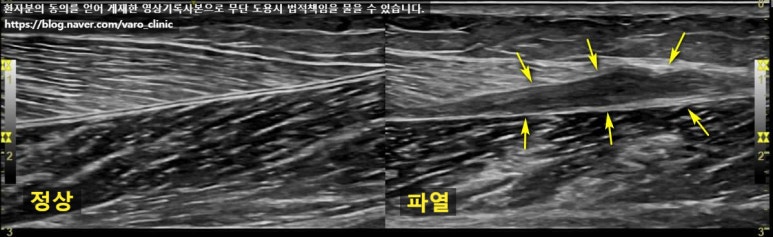

아래 사진은 정형외과에서 초음파 검사 후 근육파열로 진단받고 한의 치료를 병행하고자 내원하셨던 환자분께서 가져오신 영상으로, 양측 종아리를 비교한 사진입니다.

좌측 그림은 정상적인 비복근의 모습이고요. 우측 그림에서 비복근과 그 아래의 근막사이가 벌어진 파열부위가 확연하게 보입니다. 검사를 받으셨다면 영상CD를 지참해서 내원하시고, 검사를 아직 받지 않으셨다면 한의원에서 진료 후 적절한 검사를 협력 병원에 의뢰합니다.